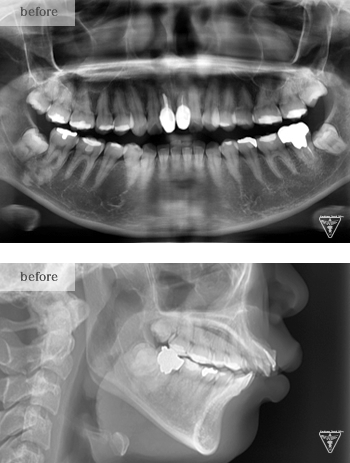

20代女性:AngleⅡ級の症例

治療前

初診時での口腔内所見